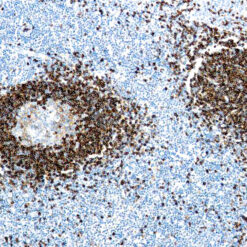

Solitary fibrous tumor (SFT) is a fibroblastic neoplasm of variable biologic potential that can arise at a wide range of anatomic sites. Almost all cases of (98%) including conventional, cellular, atypical, and malignant variants showed nuclear expression of STAT6. Staining for STAT6 was usually diffuse: 68% of cases showed reactivity for STAT6 in 75% of tumor cells. Further, the intensity of staining was strong in 67% of cases, moderate in 25%, and weak in only 7%. The heterogeneity of staining, both in terms of extent and intensity, which may be because of uneven tissue fixation or loss of antigenicity in older cases for which the unstained slides were stored for extended periods of time. All other tumor types examined were negative for STAT6, except for three dedifferentiated liposarcomas and one deep fibrous histiocytoma, which showed weak staining. STAT6 is therefore a highly sensitive and almost perfectly specific immunohistochemical marker for SFT, and can be helpful to distinguish this tumor type from histologic mimics.

| Positive Control Tissue | Solitary fibrous tumor |